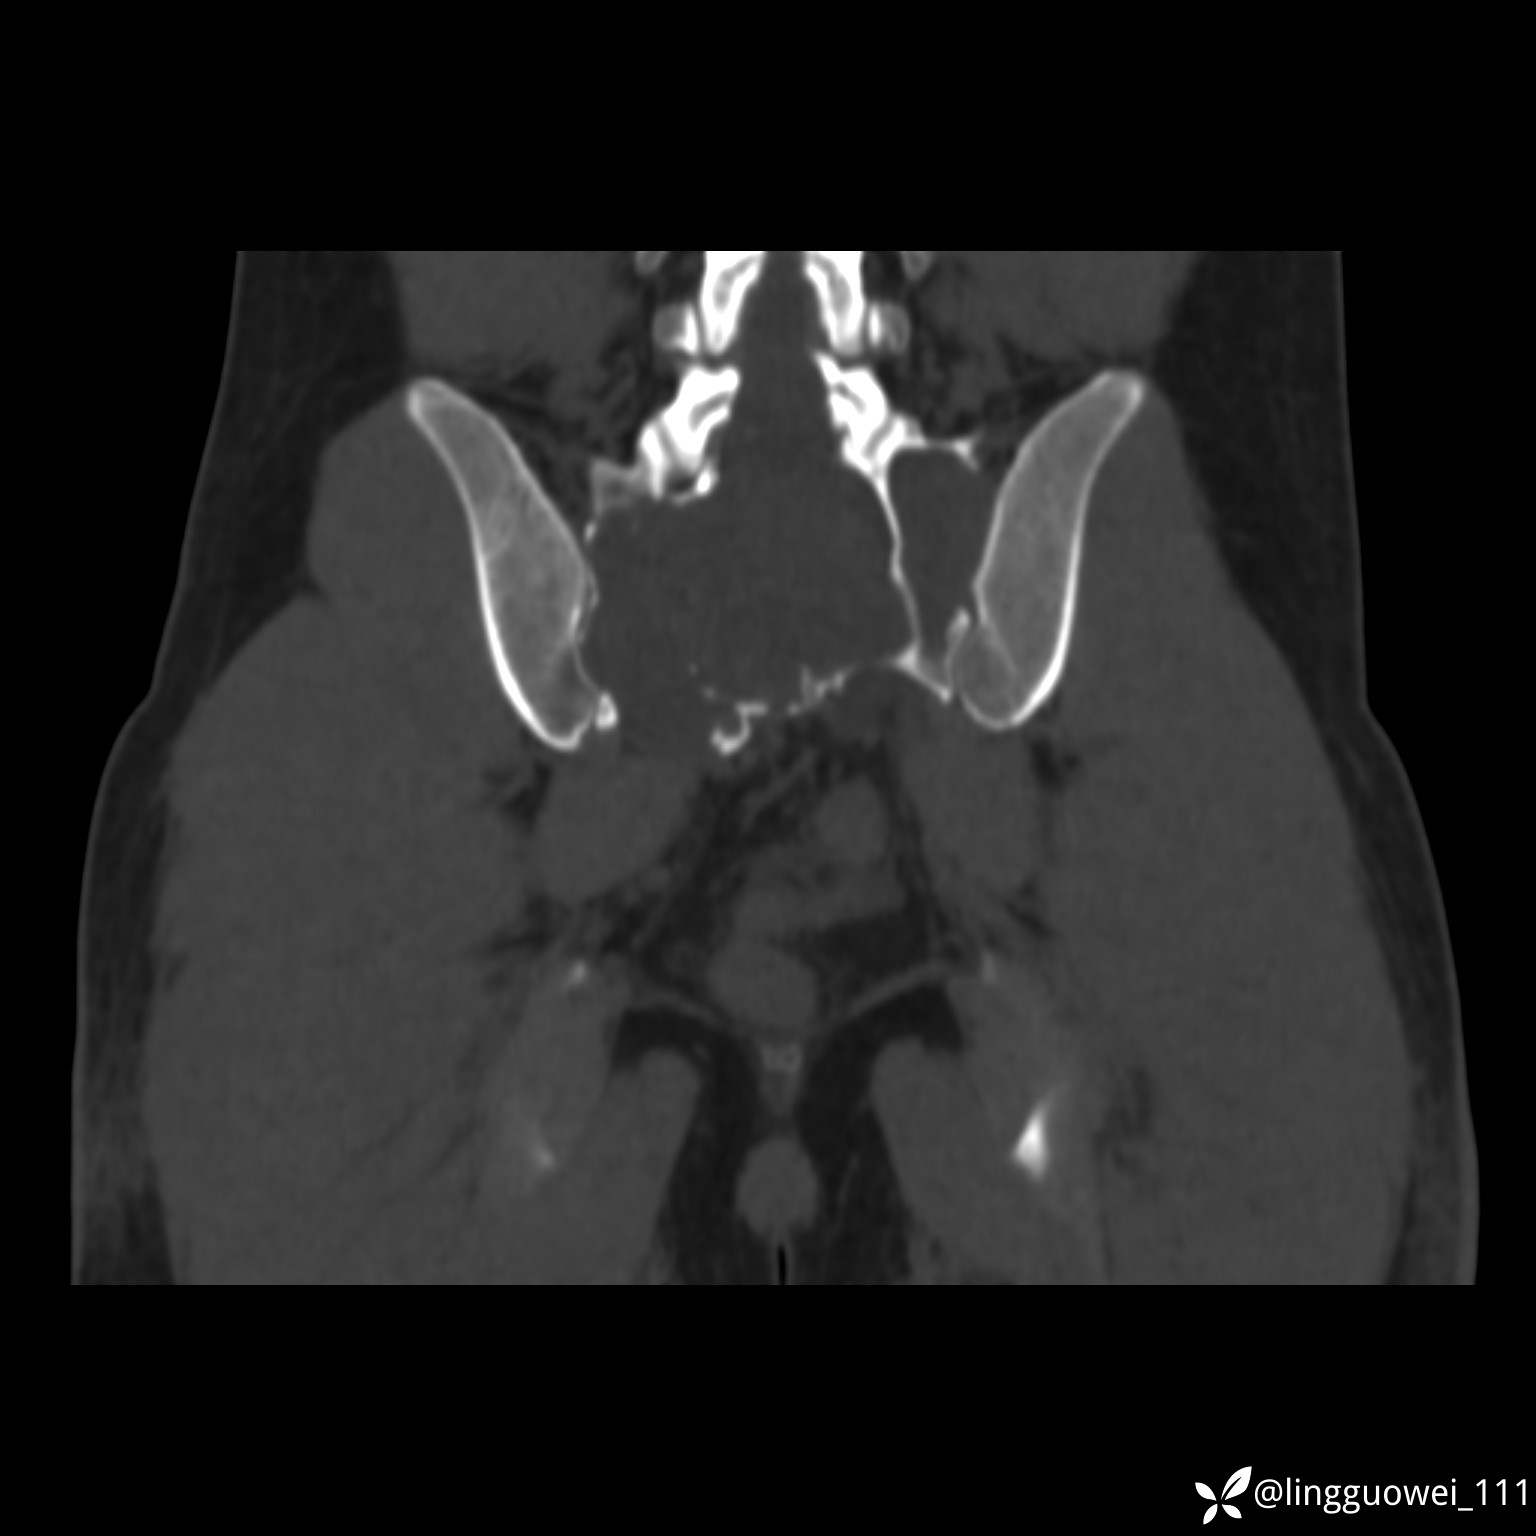

静脉期:

img